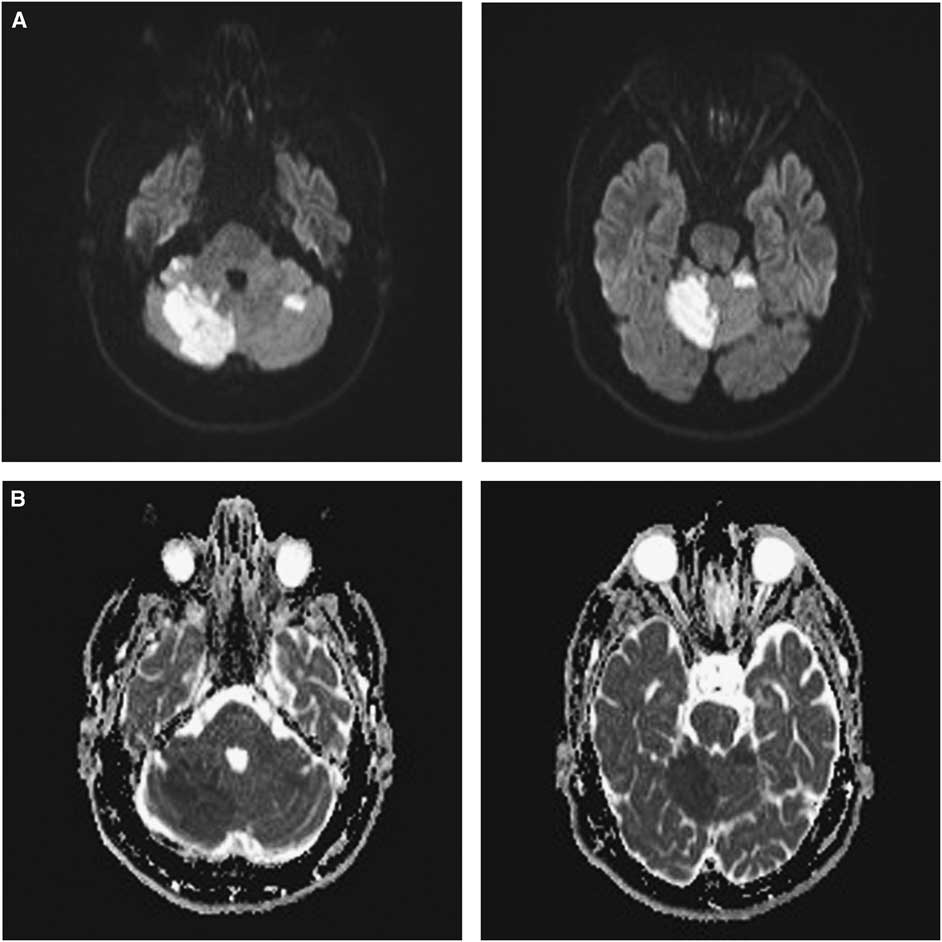

Figure 1 Multiple acute brain infarcts in a patient with congenital afibrinogenemia. (A) Diffusion-weighted imaging (DWI) showing diffusion restriction in the right and left cerebellar hemispheres and the cerebellar vermis. (B) Corresponding apparent diffusion coefficient showing hypointensities in the same regions with diffusion restriction on DWI, supporting that they are due to acute infarction.

A 36-year-old man with congenital afibrinogenemia and a previous left middle cerebral artery (MCA) stroke presented to the hospital with new headache, binocular diplopia and vertigo. He was taking clopidogrel with reported good adherence, but while he was scheduled to receive fibrinogen concentrate weekly his adherence was poor. Neurological examination revealed restricted right eye abduction and elevation. Right hemiparesis, dysarthria, impaired gait and upper motor neuron findings could not be differentiated from the residual deficits of his prior stroke. CT of the head only showed the known previous left MCA stroke. MRI confirmed new strokes. Diffusion-weighted imaging showed multiple acute infarcts with restricted diffusion in the superior right cerebellar hemisphere, inferior right cerebellar hemisphere, cerebellar vermis, left cerebellar hemisphere, left occipital lobe and right parietal lobe (Figure 1A). These regions appeared hypointense on apparent diffusion coefficient (Figure 1B), suggesting that they were due to acute infarction. The right superior cerebellar artery was irregular distally on the CT angiogram, but otherwise no new relevant vessel anomalies were reported. The other older vessel anomaly is chronic occlusion of the left internal carotid artery with tandem occlusion of the left mid-to-distal M1 MCA, but there was no acute branch vessel occlusion seen otherwise in this region. Transthoracic echocardiogram was unremarkable; the patient did have surgical repair of a patent foramen ovale at least 8 years before this presentation, but the exact date of the repair is unknown. As the patient’s fibrinogen level was low at 0.3 g/L (normal 1.9-4.1 g/L), he received the fibrinogen concentrate. As new infarcts occurred while the patient was on clopidogrel, apixaban (5 mg twice daily) was started with the intent for him to remain on lifelong anti-coagulation.